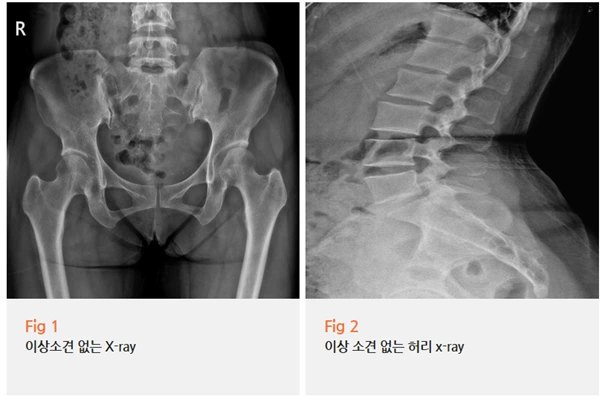

당일 X-Ray 검사까지 한 결론은 뭐였을까요?

콕통증의학과에서는 이분을 외상성 이상근증후군으로 진단했어요.